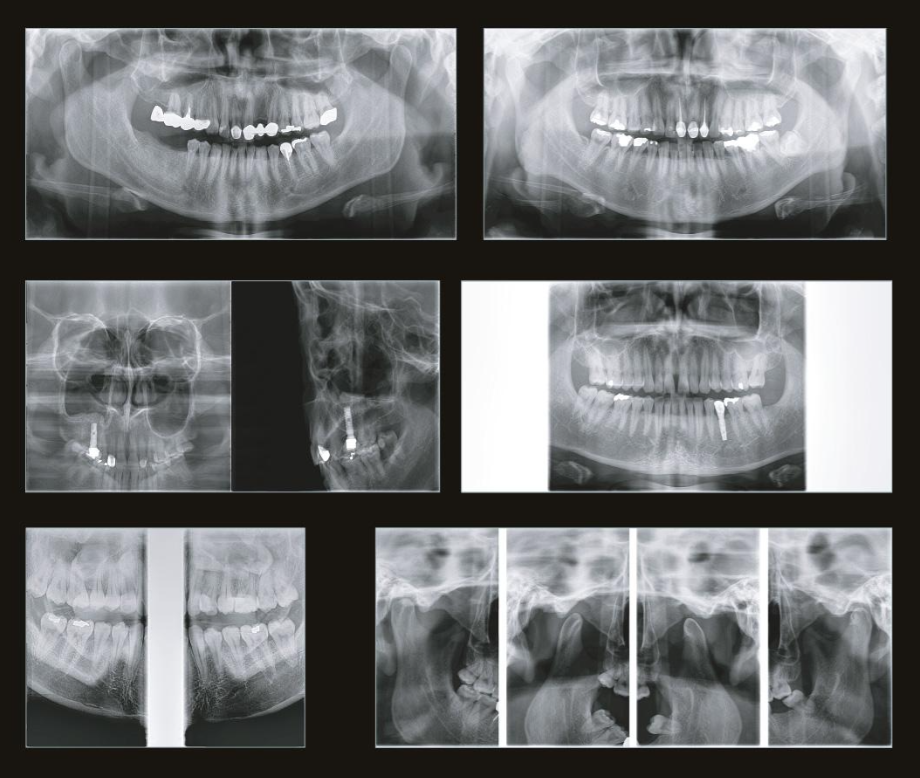

- Виды исследований: Панорама, КТ, цефалометрия

70 мкм в Эндодонтическом режиме 3,5×4 см

Высокотехнологичный детектор с самым высоким разрешением в классе – 70 мкм. Позволяет различить даже самые мелкие анатомические образования и облегчит постановку диагноза в сложных случаях. А вместе с применением алгоритма SMARF инородные тела из металла не испортят качество снимков.

Умная Функция Уменьшения Артефактов от Металла (Smart Metal Artifact Reduction Function) – позволяет минимизировать артефакты от вторичного излучения металлов и получить необходимую диагностическую информацию для постановки корректного диагноза, а также планирования и контроля проведенного лечения.

Помимо стандартных функций проведения КТ и Панорамы, томограф также оборудован цефалостатом. Он предназначен для анализа и интерпретации рентгеновского снимка. С этим устройством процесс постановки диагноза и лечения станет намного точнее и качественнее.

Для полного обследования и более точной постановки диагноза программное обеспечение TRIANA позволит более грамотно и поэтапно построить весь путь лечения. Программа позволяет рассматривать в мелких деталях все необходимые места с разных ракурсов. С ним процесс лечения станет более полным и достаточно быстрым.

Широкий функционал

Устройство оснащено множеством функций, позволяющих проводить качественное и всестороннее обследование. Специально для стоматологов томограф поддерживает эндодонтический режим. Эта функция позволяет делать снимки в разрешении 70 мкм. Снимок получается размером 3,5×4 см. Высокую чувствительность на снимках обеспечивают сенсоры из теллурида кадмия.

Металл больше не помеха

Зачастую частицы металла портят результаты сканирования. Однако с новой технологией SMARF об этой проблеме можно забыть. Умная система убирает помехи от излучения металла, делая картинку четкой и подробной. Благодаря ей у вас на руках будет вся необходимая диагностическая информация.